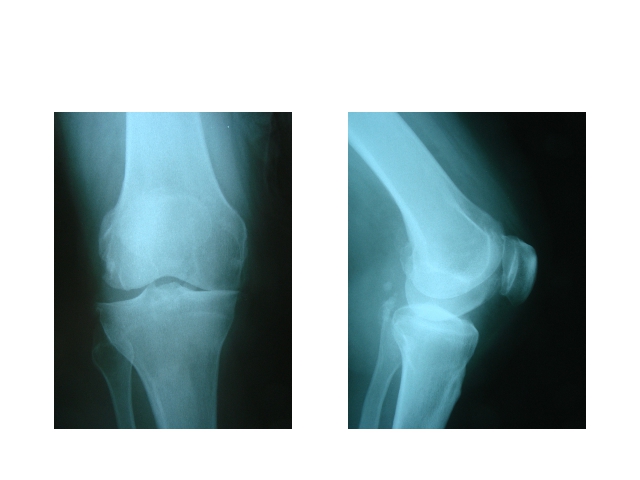

Hip and Knee ProsthesisDec 30, 2021 | Case ExamplesKnee Prosthesis Revisions Total Knee Prosthesis Unikondiler